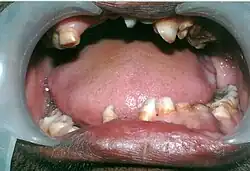

Mouth showing many over-retained deciduous teeth and some missing teeth.